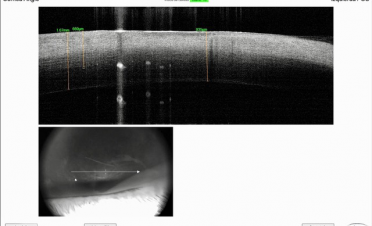

Se realizó una tomografía de coherencia óptica (OCT) para determinar el espesor de la córnea. En las imágenes se puede ver cómo el espesor de la córnea de Bagheera estaba aumentada de tamaño por la inflamación provocada por la infección.